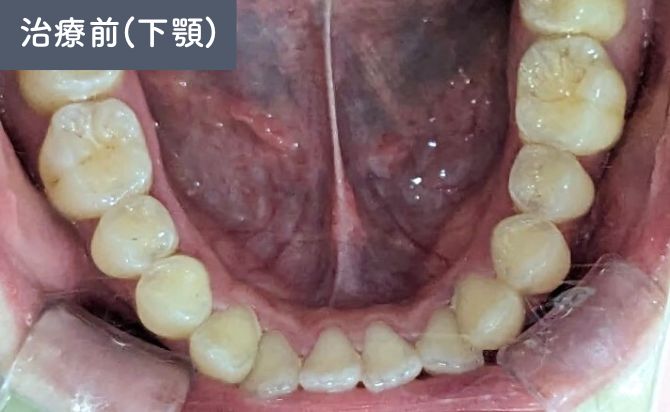

歯並びの変化(下)

口元の評価では、上顎前歯の前方位が認められ、軽度〜中等度の上下顎前突(出っ歯) が確認されました。

前歯の傾斜が強く、上唇の突出感にも影響していましたが、歯列全体のスペース不足は軽度であり、非抜歯での整列および前方位の改善が可能な状態 と判断しました。